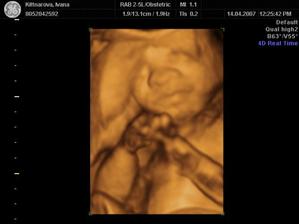

Někdy kolem 12. července by se nám mělo narodit naše první miminko. Všichni se už moc těšíme :o)

Podle ultrazvuku ve 20.tt by to měl být chlapeček.